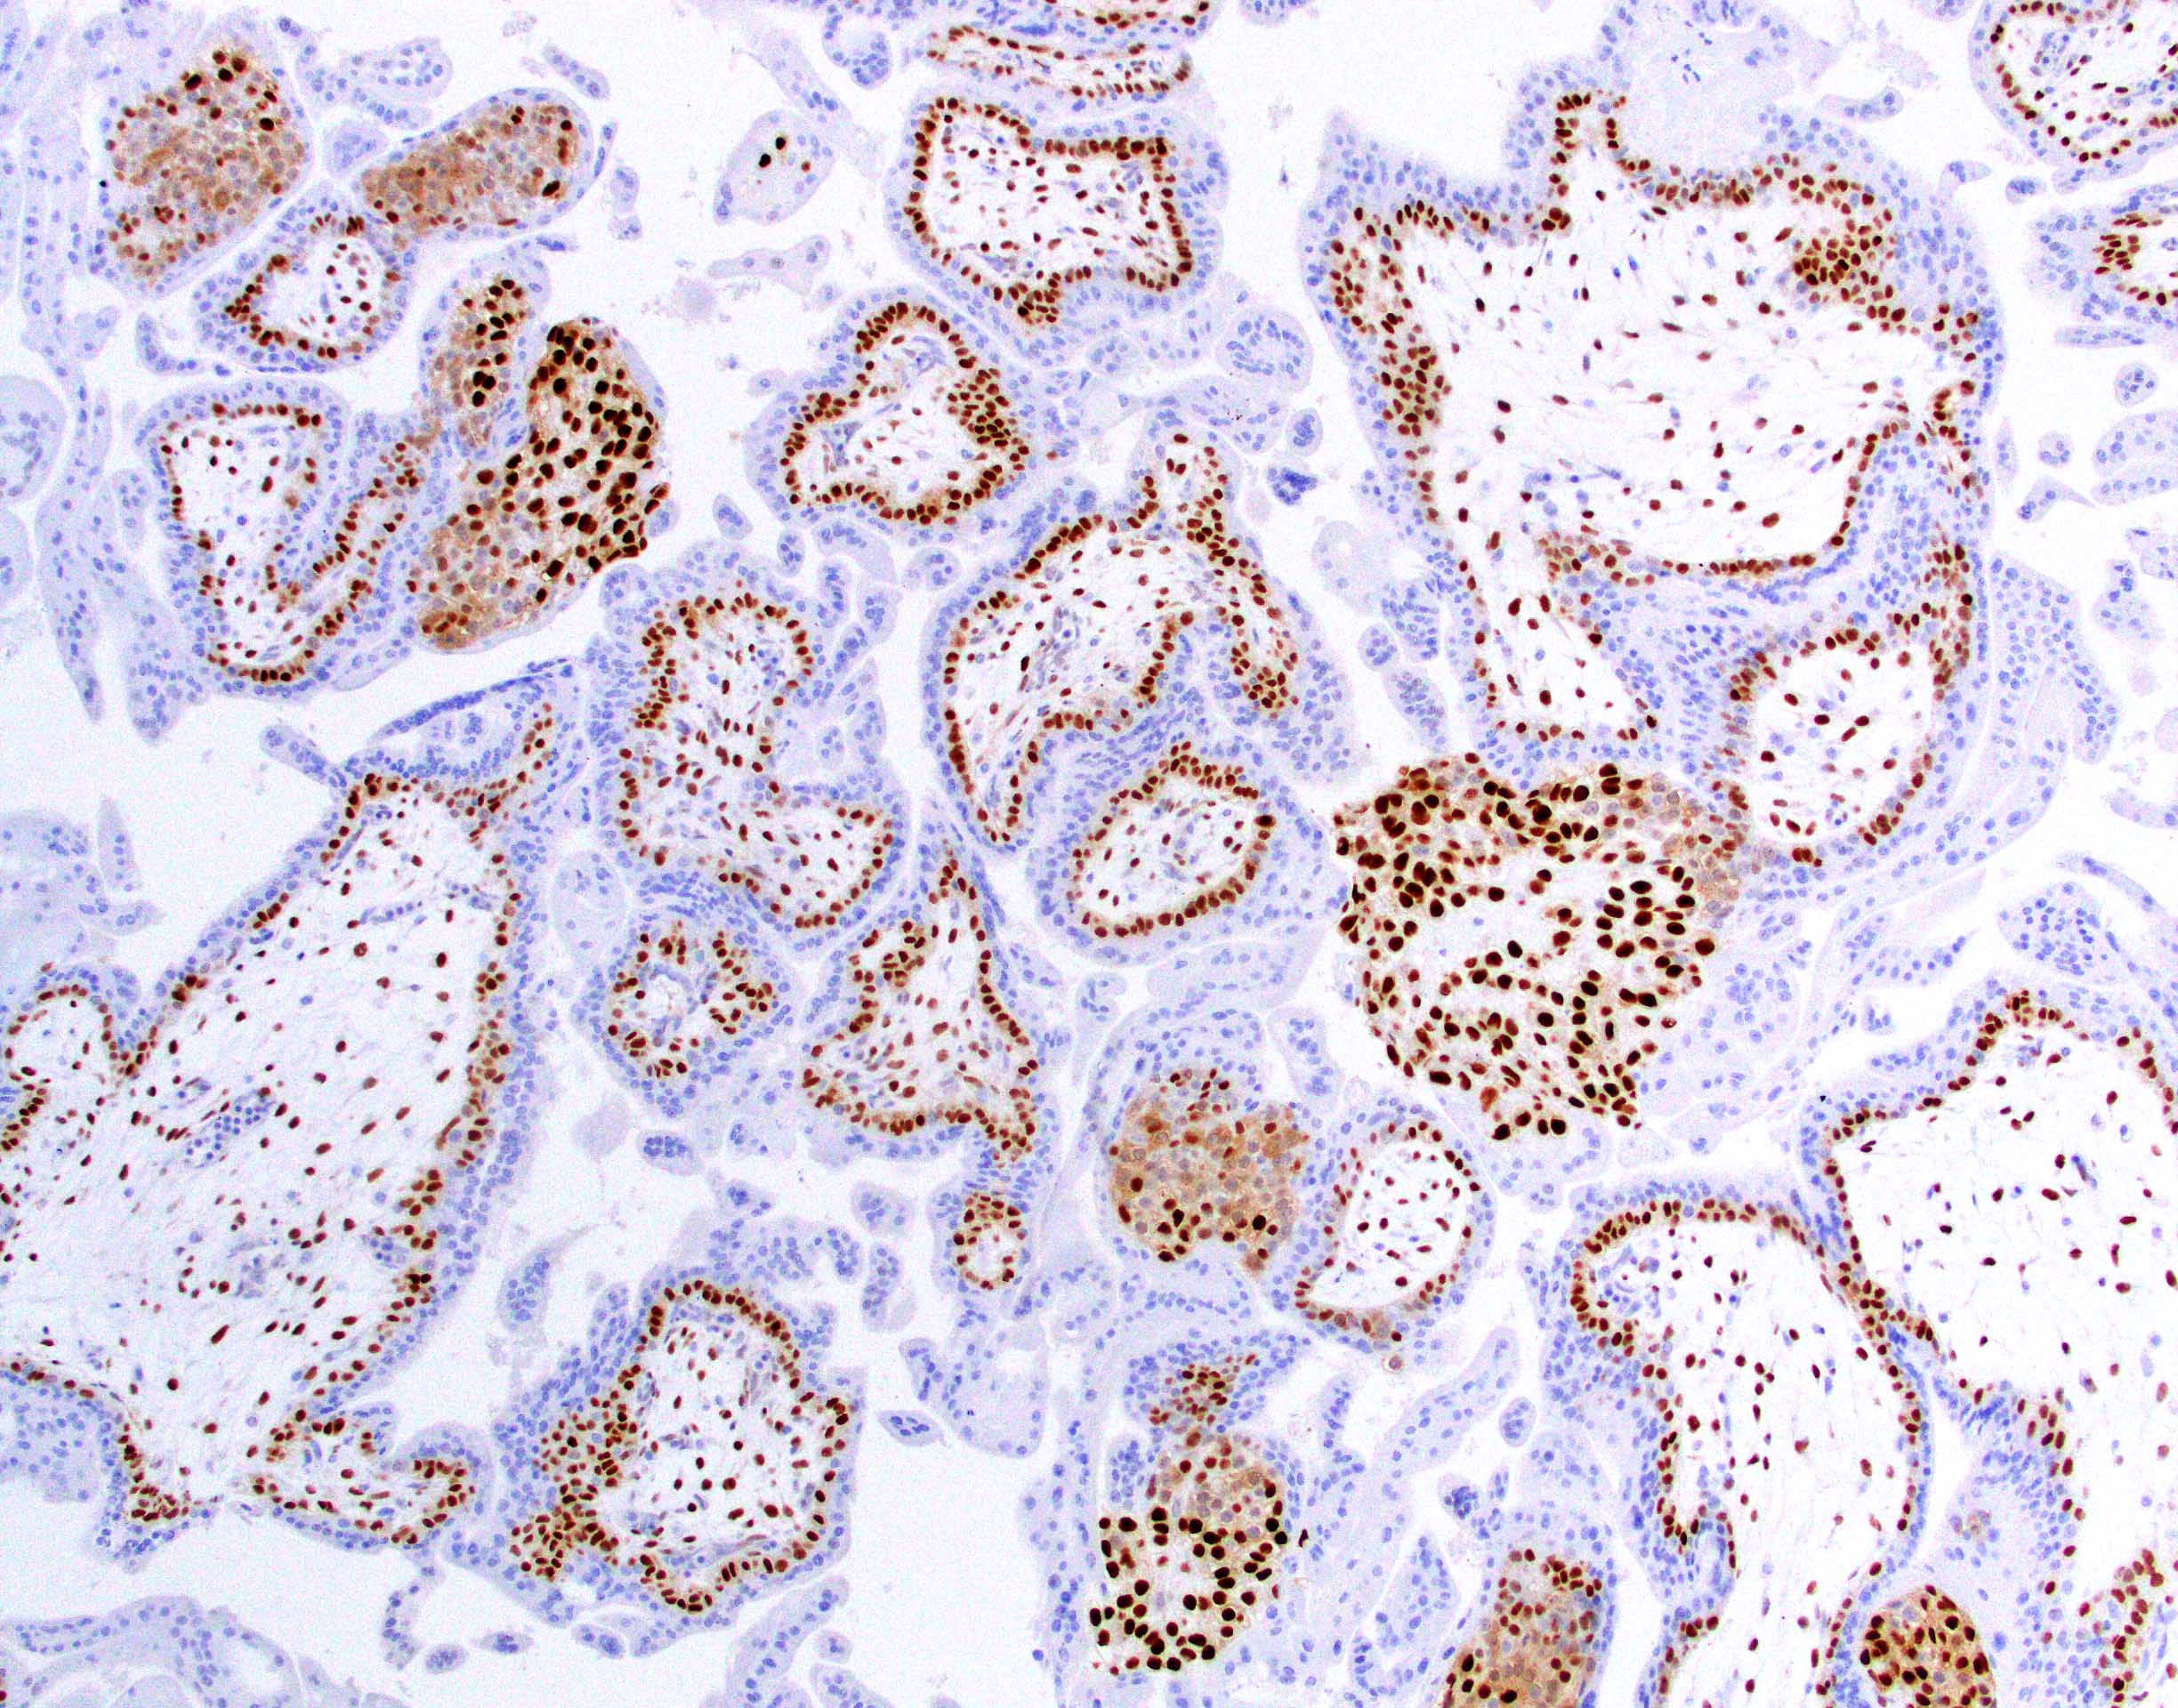

Microscopic (histologic) images

Contributed by Chrystalle Katte Carreon, M.D. and Drucilla J. Roberts, M.D.

- Loss of the normal nuclear p57 staining in cytotrophoblasts and villous stromal cells; therefore, p57 immunostain is often helpful in distinguishing complete mole (absence of the normal pattern of staining in chorionic villi) versus edematous villi (normal pattern of staining with nuclear staining in villous cytotrophoblasts and stromal cells